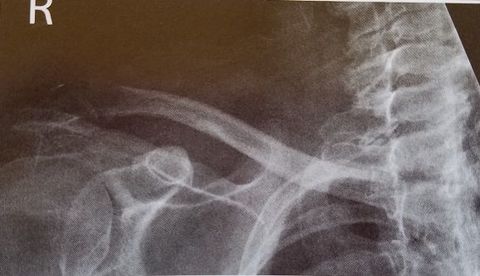

| AP Shoulder internal rotation | the MCP is tilted posteriorly as marked by the superior scapular angle is inferior to the clavicle |

| AP Shoulder | patient is rotated towards the unaffected shoulder: decreased thoracic superimposition over the scapular body |

| AP Shoulder | patient is rotated towards affected side:increased thoracic superimposition over the scapular body |

| Inferosuperior Axiolateral Shoulder | humerus is foreshortened - humeral head is distorted arm is not abducted 90 degrees from body |

| Grashey | Insufficient obliquity |

| Grashey | Excessive obliquity |

| Grashey | MCP is tilted posteriorly |

| PA Oblique Scapular Y-Lateral | Excessive Obliquity |

| PA Oblique Scapular Y-Lateral | Insufficient Obliquity |

| PA Oblique Scapular Y-Lateral | MCP is tilted anteriorly |

| PA Oblique Scapular Y-Lateral | MCP is tilted posteriorly |

| AP Clavicle | MCP is tilted anteriorly |

| AP Clavicle | MCP is tilted posteriorly |

| AP Clavicle | Patient is rotated towards affected shoulder |

| AP Clavicle | Patient is rotated towards unaffected shoulder |